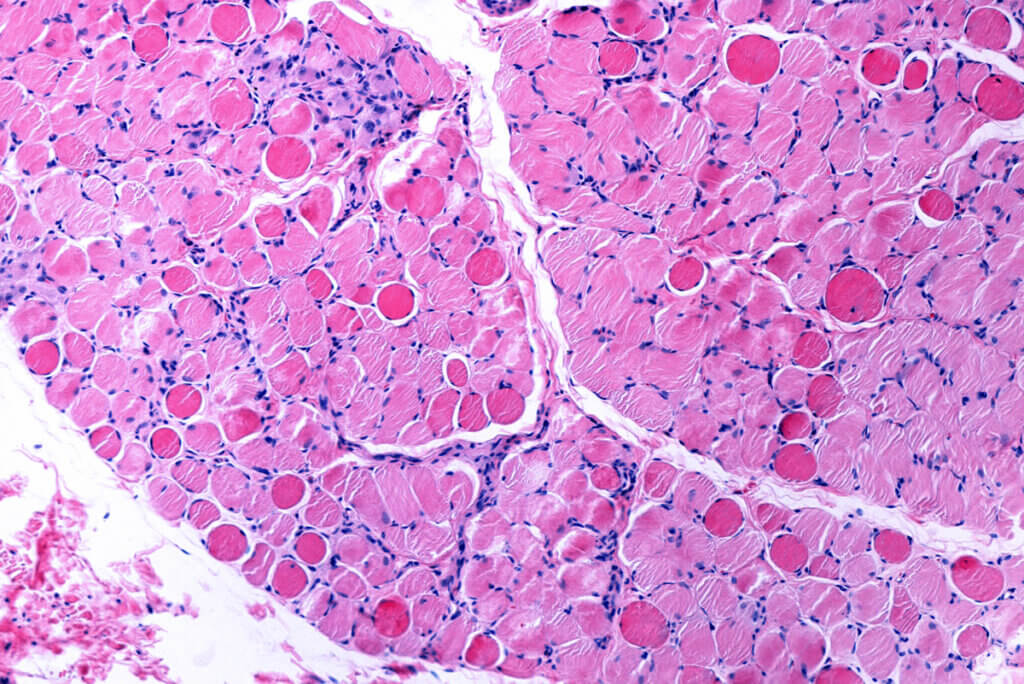

Volgens de wetenschap (Engelse link) is het een van de meest invloedrijke stoffen als het gaat om spiergezondheid. Het neemt deel aan weefselreconstructie en verhoogt de functionaliteit ervan.

Het is niet alleen in staat om de sportprestaties te beïnvloeden, maar leucine kan ook het risico verminderen op het ontwikkelen van pathologieën die optreden bij het geleidelijke verlies van vetvrije massa. Een voorbeeld is het geval van sarcopenie. Suppletie met het aminozuur zou in deze situatie zelfs een effectieve behandeling kunnen zijn, volgens een studie gepubliceerd in Nutrients (Engelse link).

We mogen ook de noodzaak om regelmatig aan lichaamsbeweging te doen niet vergeten. Krachttraining is wat de meeste impact op de spieren heeft, waardoor deze gedwongen worden zich aan te passen en de doorsnede ervan te vergroten. Onthoud dat een goede spierkrachtwaarde geassocieerd is met een lager risico op sterfte door alle oorzaken.